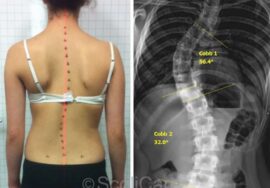

أجريت دراسة حديثة شملت 91 فتاة مراهقة، نصفهن مصابات باعوجاج العمود الفقري مجهول السبب، والنصف الآخر فتيات سليمات للمقارنة.

كما تم قياس زاوية “كوب” (Cobb angle) من الأشعة السينية لمعرفة شدة الانحناء.

كشفت النتائج أن الفتيات المصابات باعوجاج العمود الفقري أظهرن ضعفًا واضحًا في تحمل عضلات الجذع مقارنة بالفتيات السليمات:

قوة عضلات البطن كانت أقل بنسبة 43%.

قوة عضلات الظهر كانت أقل بنسبة 32%.

أي أن الفتيات المصابات يعانين من ضعف مزدوج في كل من عضلات البطن والظهر، مما يجعل العمود الفقري أقل استقرارًا.

لكن المثير للاهتمام أن نسبة التوازن بين المجموعتين بقيت متقاربة؛ أي أن الضعف يحدث بشكل متوازن على الجانبين، ولا يقتصر على جهة واحدة من الجسم.